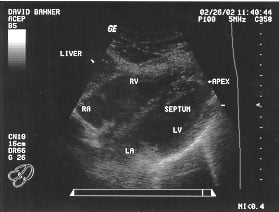

Cardiac - Subxiphoid view (labeled)